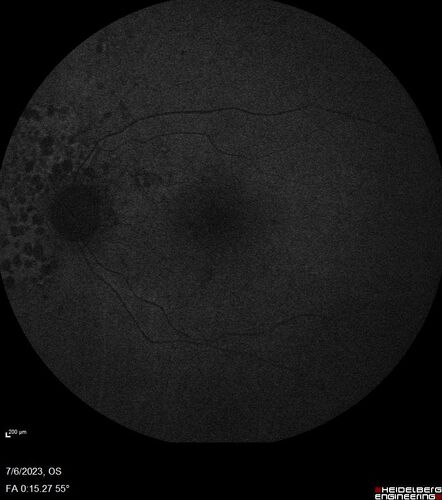

Radiation Retinopathy Both Eyes - 2023 - Two years after radiation for ocular lymphoma  (7)